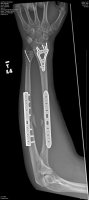

In all seriousness Ray I hope you heal up quickly. I dont know how old these images are, but man that had to really hurt like a SOB!

about 2 weeks :devil: it wasnt too bad, i manned up and didnt cry. but thank you very much!